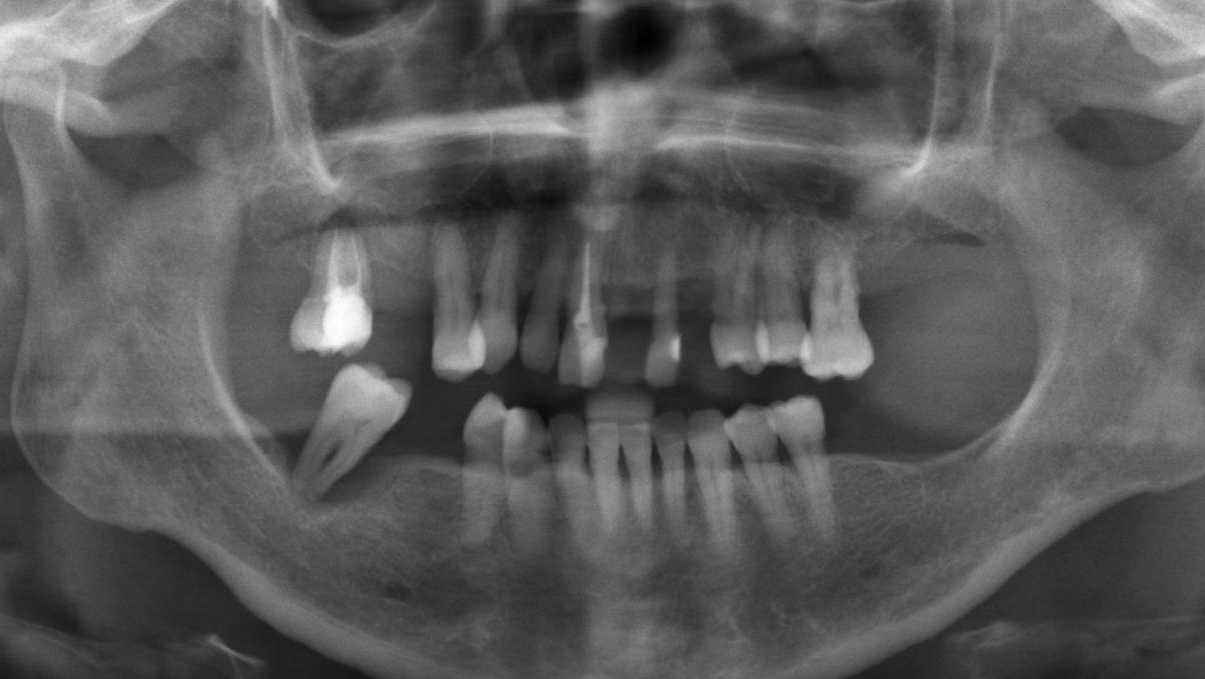

La rehabilitación oral completa en pacientes parcialmente edéntulos requiere una planificación cuidadosa, que integre tanto la función como la estética. La aplicación de técnicas mínimamente invasivas asociadas a protocolos de carga inmediata optimiza la experiencia del paciente, disminuye los tiempos clínicos y facilita la recuperación de la función oral, con resultados estables y predecibles.

En el caso presentado, la utilización de implantes monobloque Easy-Link en el maxilar superior, combinados con implantes convencionales atornillados en el maxilar inferior, permitió alcanzar una rehabilitación integral ajustada a la anatomía y a las necesidades específicas de la paciente.